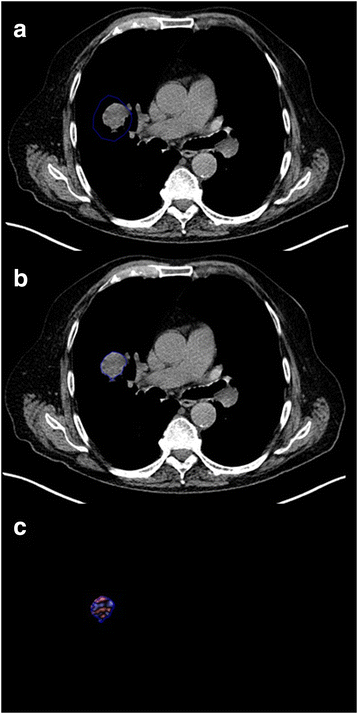

When using automatic segmentation for tumour Regions of Interest (ROIs), the initial manually constructed ROI (a) can include surrounding lung. The segmentation software then redifines the ROI to exclude lung tissue b. The filtered tumour image (c) is used for derivation of texture parameters by histogram analysis

The potential for prognostic biomarkers to stratify care for patients with NSCLC. CT showing left upper lobe NSCLC at initial staging a. Based on current practice, the patient underwent surgery without adjuvant chemotherapy. CT performed 25 months later shows local recurrence b. A biomarker deployed at staging may have categorised the patient as high-risk for recurrence, implying a potential benefit from adjuvant chemotherapy